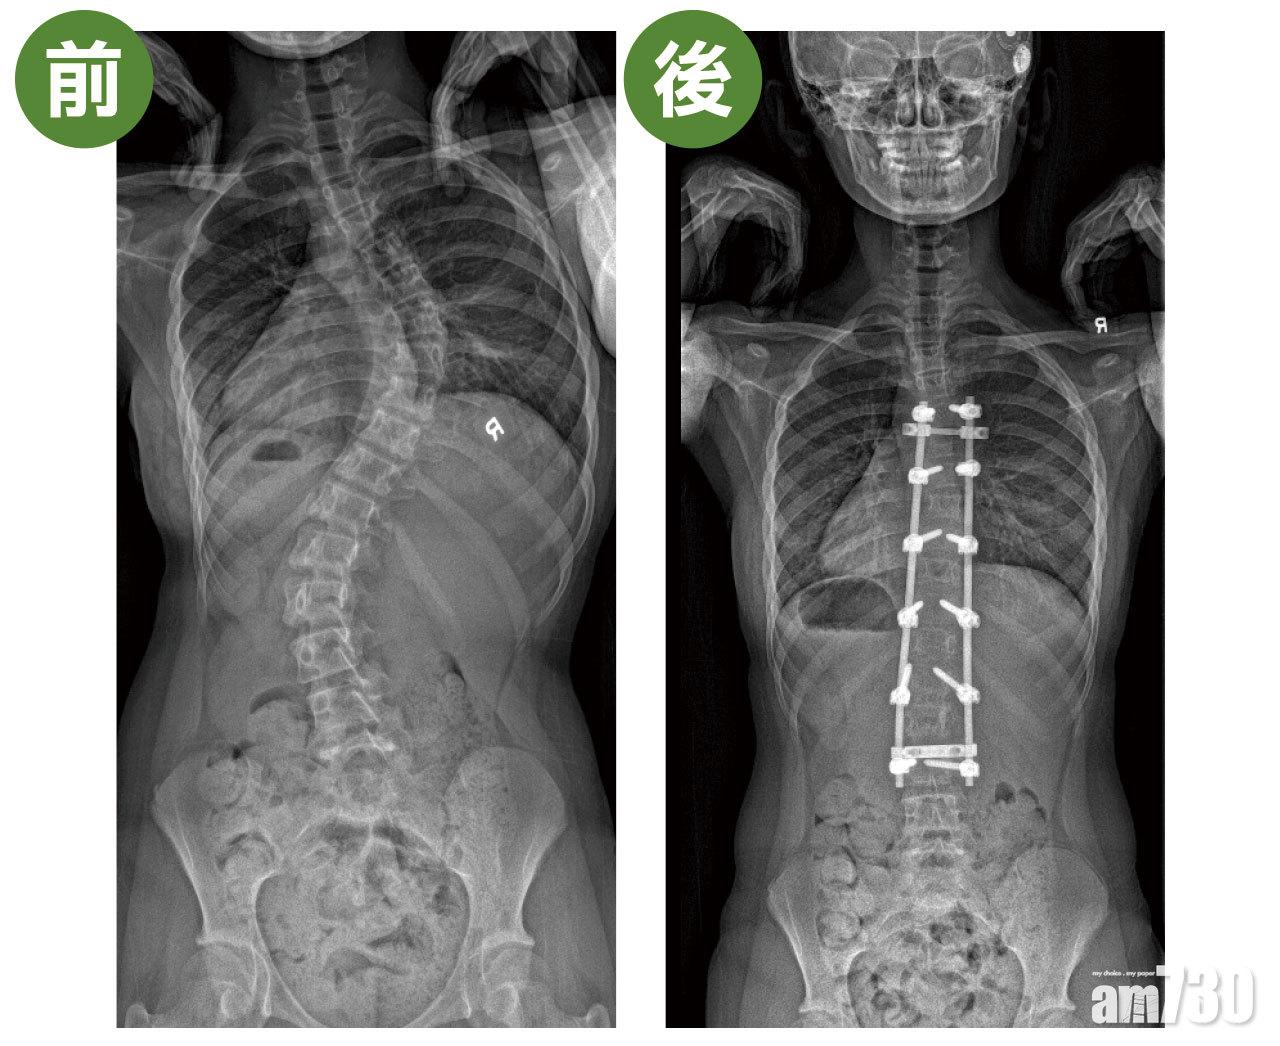

13歲的晴晴(化名)一直不知道自己脊柱有毛病,直到某次游水,媽媽發現她的脊骨向左邊嚴重彎曲,有高低膊和肋骨拱起,於是帶她求診。經臨床診斷及X光檢查,確診是俗稱「C」型的脊柱側彎,弧度達64度(正常是0度)。由於晴晴已來經一年,過了發育階段,骨齡比較大,加上她脊柱側彎嚴重,所以不適合用保守性治療,手術是唯一方法。

晴晴採用開放式手術,於胸椎第2至第12節植入螺絲,拉直脊柱曲線,並進行脊柱融合。手術後3日她已經可以落床,第6日出院。關日康表示,「一般來說,學童休息兩星期便可復課,3個月後可以上體育堂,待半年後脊骨完全融合,就可回復一切正常活動。」

手術前,患者脊柱側彎嚴重,身體開始出現傾側的情況。手術治療透過在胸椎植入螺絲,拉直脊柱曲線。